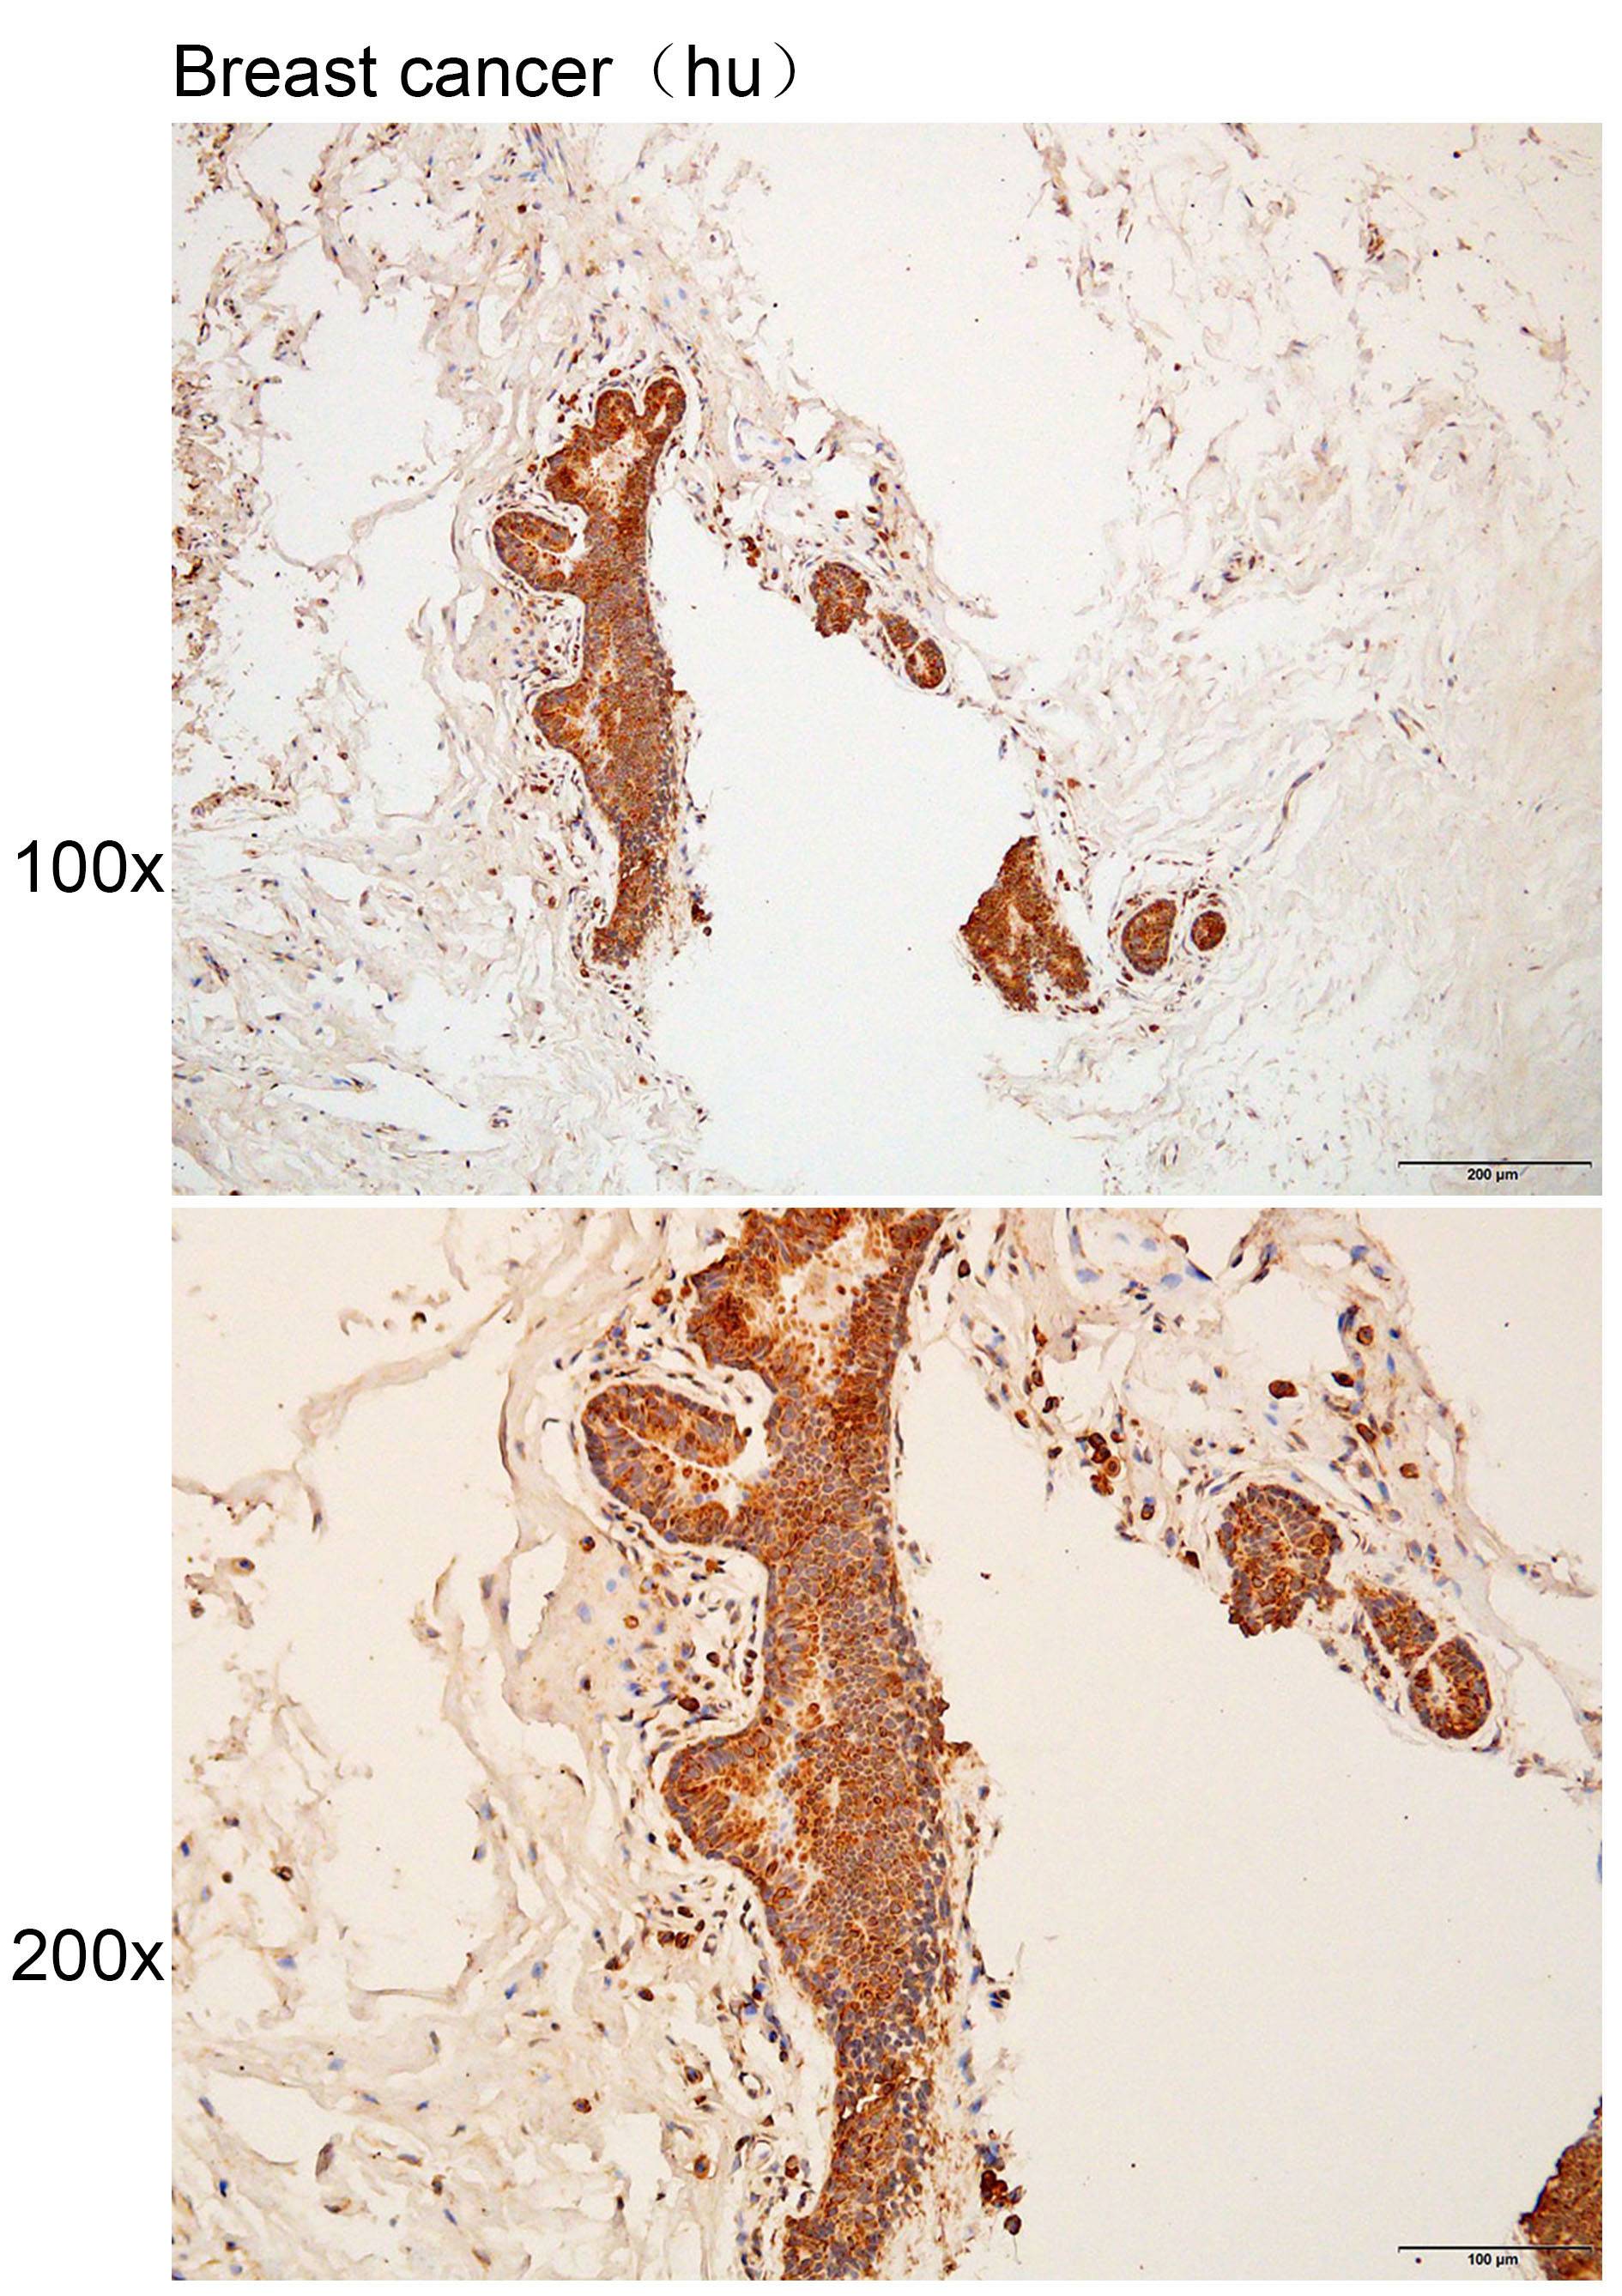

Immunohistochemistry of paraffin-embedded Human breast cancer with ADGRD1 antibody diluted at 1:100